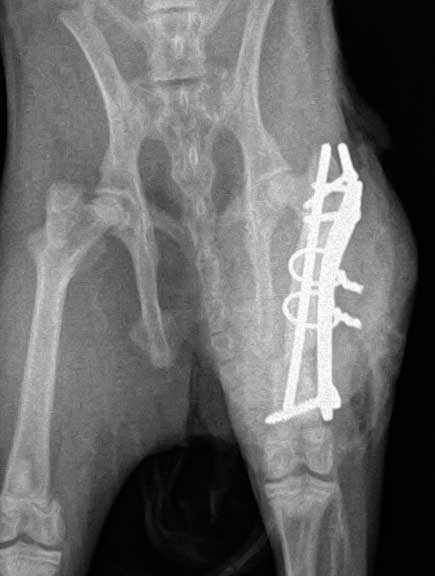

What a bone plate looks like on a dog’s fractured femur. Lots of screws are used, and they all need to be sterile since the plate and screws might stay in a long time.

Can you visualize the 3 screws and 2 cerclage wires over the bone plate in this post operative VD (venture-dorsal) radiograph of the pelvis?

This is the lateral view of the plate